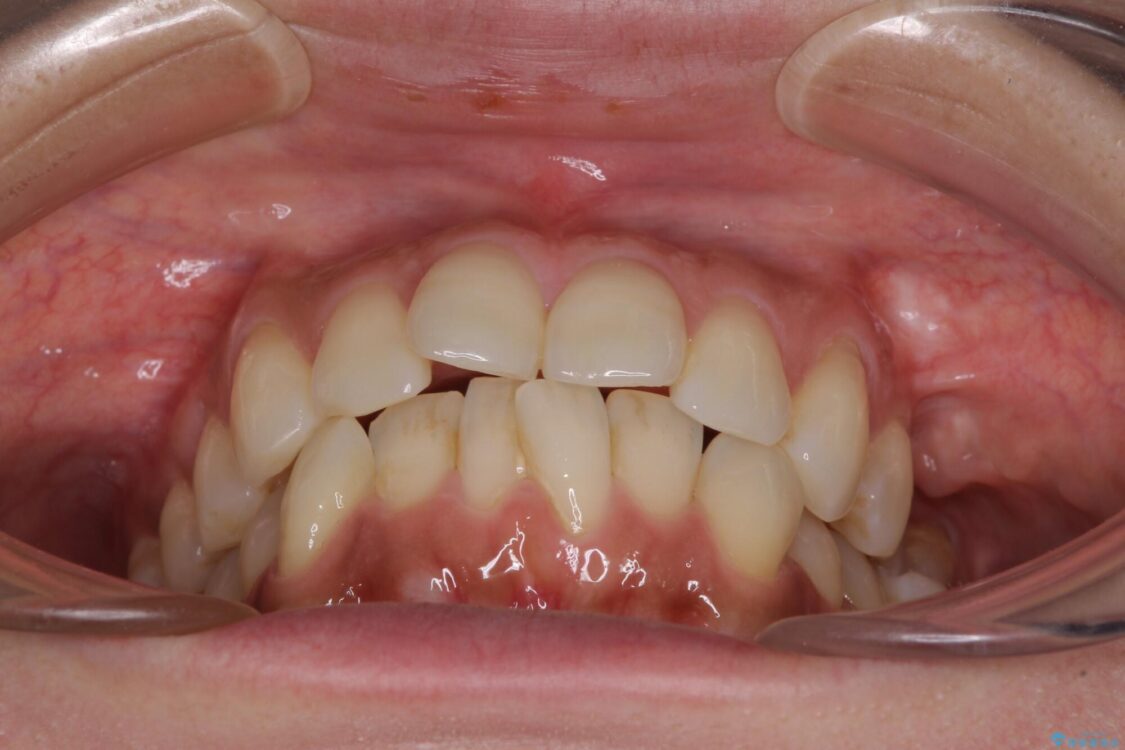

治療後について

歯の傾斜が改善され、インプラントによるクラウンが装着されたことで、物が挟まることもなくなりました。

治療後

• インビザラインによる矯正治療と奥歯のインプラント治療 治療後画像